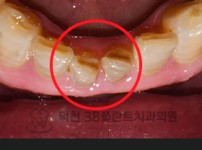

치료전후